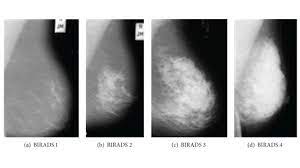

Looking For Clues About The Dangerous Breast Cancers That Turn Up Between Mammograms Los Angeles Times from ca-times.brightspotcdn.com (a) almost entirely fatty breast tissue, found in about 10% of women. It said 1 million women. The study determined that the sweet spot for finding breast cancer is in the recall range of 12 to 14 percent, compared to the current guidelines of 5 to 12 percent. Of all women who receive regular mammograms, about 10 percent will get called back for further testing and of those, only about 0.5 percent will be found to have cancer. Breast cancer is the most common type of cancer in women in the united states, accounting for 1 of every 3 cancers diagnosed. Your chances of being diagnosed with cancer after a callback are small, but your doctor wants to be sure there is no cancer present. Ten percent of women return and of that percentage only 8 to 10 percent are biopsied. (b) scattered areas of dense glandular tissue and fibrous connective tissue ( scattered fibroglandular breast tissue) found in about 40% of women.

This equates to an overall 0.5% chance of being diagnosed with cancer after undergoing a screening mammogram. The average size of breast cancer, when found on mammograms, is 1.1 cm. Breast cancers are sometimes detected when very small by the presence of microcalcifications in the breast. Hi, i was diagnosed the same as you i'm 51 and it was my first mammogram they found calsifications in right breast. Getting called back for additional mammogram views or a biopsy is pretty common and doesn't necessarily mean you have cancer. 14 dec 2019 22:16 in response to westcoastwife. (a) almost entirely fatty breast tissue, found in about 10% of women. Breast cancer is the most common type of cancer in women in the united states, accounting for 1 of every 3 cancers diagnosed. Breast cancer is one of the most common cancers in western new york, affecting 1 out of every 8 women (12.5%). State that screening reduces breast cancer mortality by 20% or more, because it sounds more impressive than explaining that the absolute risk reduction is 1 in 1,000. Health, united states, 2019, table 33. (b) scattered areas of dense glandular tissue and fibrous connective tissue ( scattered fibroglandular breast tissue) found in about 40% of women. Overall, the sensitivity of mammography is about 87 percent 31 .

Biennial Mammography Screening Yields More Advanced Stage Cancers Imaging Technology News from www.itnonline.com The percentages are on a woman's side when it comes to mammograms and breast cancer diagnosis. Breast cancer is the most common type of cancer in women in the united states, accounting for 1 of every 3 cancers diagnosed. 24% of women who had yearly mammograms were diagnosed with stage ii, iii, or iv breast cancer 44% of women who had mammograms every 2 years were diagnosed with stage ii, iii, or iv breast cancer women who had mammograms every 2 years also were diagnosed with larger cancers. If you have dense breast tissue, the odds of the cancer being missed on mammography start going up. Breast cancers are sometimes detected when very small by the presence of microcalcifications in the breast. (a) almost entirely fatty breast tissue, found in about 10% of women. In the 1980s and 1990s, breast cancer incidence rose, largely due to increased mammography screening .breast cancer incidence declined between 1999 and 2004 .this decline appears to be related to the drop in the use of menopausal hormone therapy after it was shown to increase the risk of breast cancer . Hi, i was diagnosed the same as you i'm 51 and it was my first mammogram they found calsifications in right breast.

Overall, screening mammograms miss about 20% of breast cancers that are present at the time of screening. It is one of the leading causes of cancer mortality among women in the united states. It said 1 million women. 3d mammograms and breast mris are two of the best ways for your healthcare team to keep a close watch on any breast changes or abnormalities. Luminal a tumors are associated with the most favorable prognosis Your chances of being diagnosed with cancer after a callback are small, but your doctor wants to be sure there is no cancer present. Percent of women aged 40 and over who had a mammogram within the past 2 years: (a) almost entirely fatty breast tissue, found in about 10% of women. If you have dense breast tissue, the odds of the cancer being missed on mammography start going up. A recent study of more than 1.5 million mammograms found. Breast cancers are sometimes detected when very small by the presence of microcalcifications in the breast. A woman's chance of developing invasive breast cancer at some time in her life is approximately 1 in 8 (12.4%). It can find breast cancer when it is very small, even too small to feel.

Breast cancer is the most common type of cancer in women in the united states, accounting for 1 of every 3 cancers diagnosed. It can also detect calcifications Luminal a tumors are associated with the most favorable prognosis If you have dense breast tissue, the odds of the cancer being missed on mammography start going up. 14 dec 2019 22:16 in response to westcoastwife. Accuracy of mammograms mammography is good at finding breast cancer, especially in women ages 50 and older. Not only is mammography more likely to miss cancers in women with dense breasts, but density itself is a risk factor for breast cancer. This means mammography correctly identifies about 87 percent of women who truly have breast cancer. A woman's chance of developing invasive breast cancer at some time in her life is approximately 1 in 8 (12.4%). Overall, screening mammograms miss about 20% of breast cancers that are present at the time of screening. Mammography is the most effective screening tool to detect breast cancer, especially among women 40 and older. 3d mammograms and breast mris are two of the best ways for your healthcare team to keep a close watch on any breast changes or abnormalities. Half of women have dense breast tissue, and for those women, mammogram may not be enough.